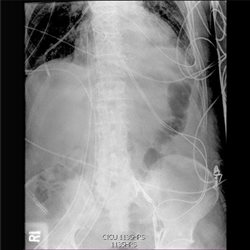

Abdominal: Plain Film 4

Various abdominal cases